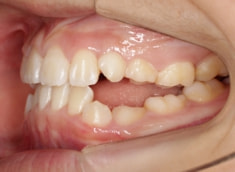

治療前

治療開始時